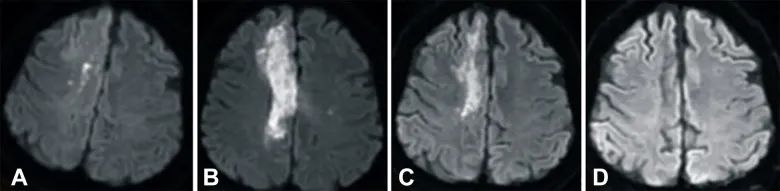

(从A到D:治疗前患者右侧放射冠有梗死,输注3个月后开始退散,6个月后消失)